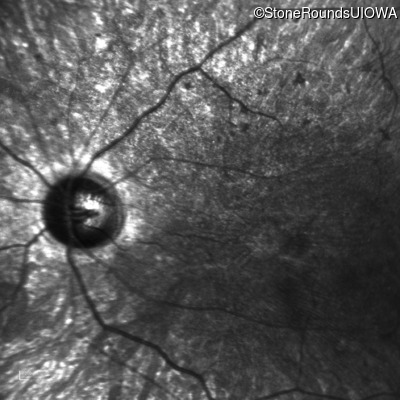

This 21 year old man first had difficulty seeing the blackboard in the 5th grade. Two years later he began having difficulty seeing in dim light. In high school he was approximately 50 pounds overweight, but was able to lose that weight with a strict diet.